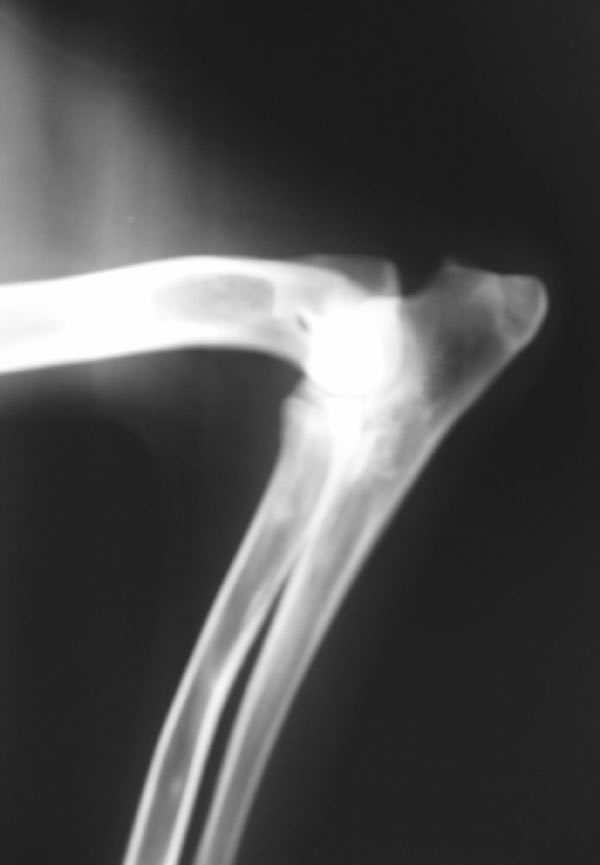

Eddy is a beautiful son of Anouc-Lar Leomegy (Nuky) and Agala Zomboch daughter of top producing stud 6XWUSV 5XFCI Emir Chabet, born December 25, 2003. He is line bred to 2XBSP Troll vom Körbelbach. He is a huge male with a very good temperament. He is good with kids and very tolerant with other animals. He likes bite work, tracking and watching Animal Planet. His obedience on field an off field is coming along very nicely. We took Eddy for his OVC certification and the veterinarian said Eddy has the best hips she's seen in five years on a GSD.

Eddy's X-Rays

OVC